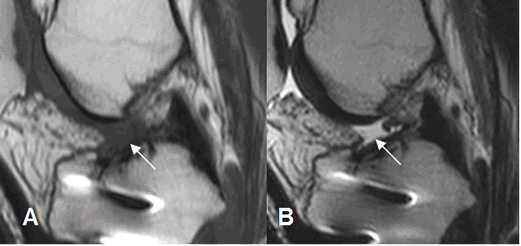

Fig 133. Túnel tibial normal.

A y B: Rx AP y C: RM coronal en T1. Orientación normal del túnel tibial, con abertura

dirigida hacia la región intercondilea.

Fig 134. Túnel tibial normal.

A y B: Rx lateral de rodilla. Orientación normal del túnel tibial, con apertura entre un cuarto y la mitad anterior del borde tibial superior.

Fig 135. Mala orientación del túnel tibial.

A: Rx lateral de rodilla y B: RM sagital en T2. Túnel muy anterior, localizado en la parte inicial de la tibia.

Fig 136. Mala orientación del túnel tibial.

A: RM sagital en T1 y B: RM sagital en T2. Túnel tibial sobre la parte posterior del borde tibial.